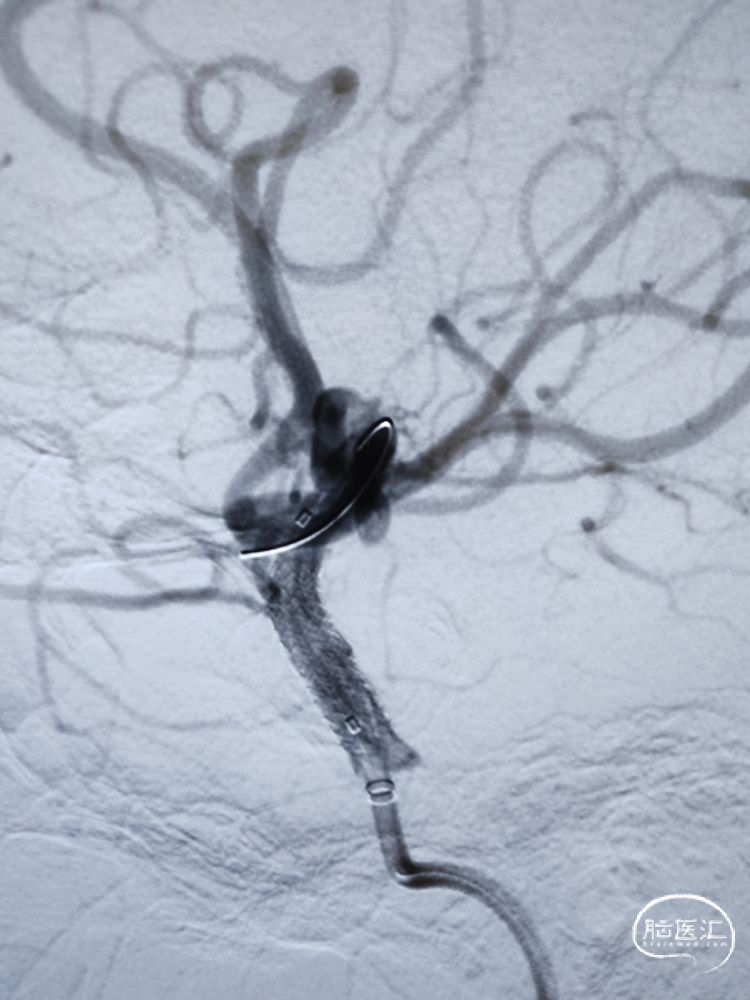

DSA检查:全脑血管造影检查提示左侧颈内动脉海绵窦段-水平段中段重度狭窄。

DSA检查:远端正常段管径约3.22mm,近端接近正常段管径约4.01mm,预估支架长度约12.67mm;合并后交通动脉圆锥。